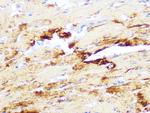

Cardiac Troponin T Monoclonal Antibody (13-11)

Invitrogen

高级验证

WB IHC IHC (P) IHC (PFA) IHC (F) ICC/IF Flow ChIP Misc

货号 MA5-12960